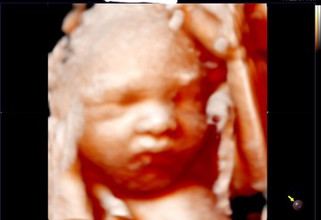

36 weeks gestational diabetes

I'm on my 36th week and I have gestational diabetes. Tinurukan kami ng steroids para makahabol ang lungs ni baby at since madaming tubig at kasing laki niya ang 39-week baby, nagwoworry ako na anytime pwede na sya lumabas kaya bedrest parin ako. May naka experience na po ba ng ganito? Safe and healthy ba si baby paglabas? Thank you po.